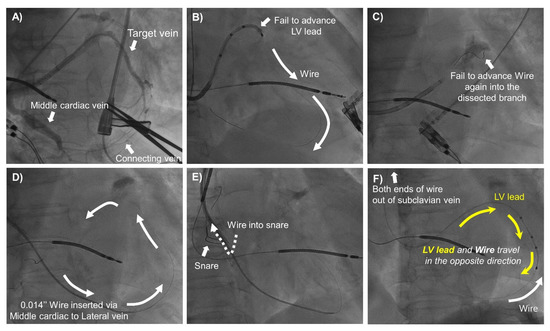

2.2. CRT Implantation and Snare Technique